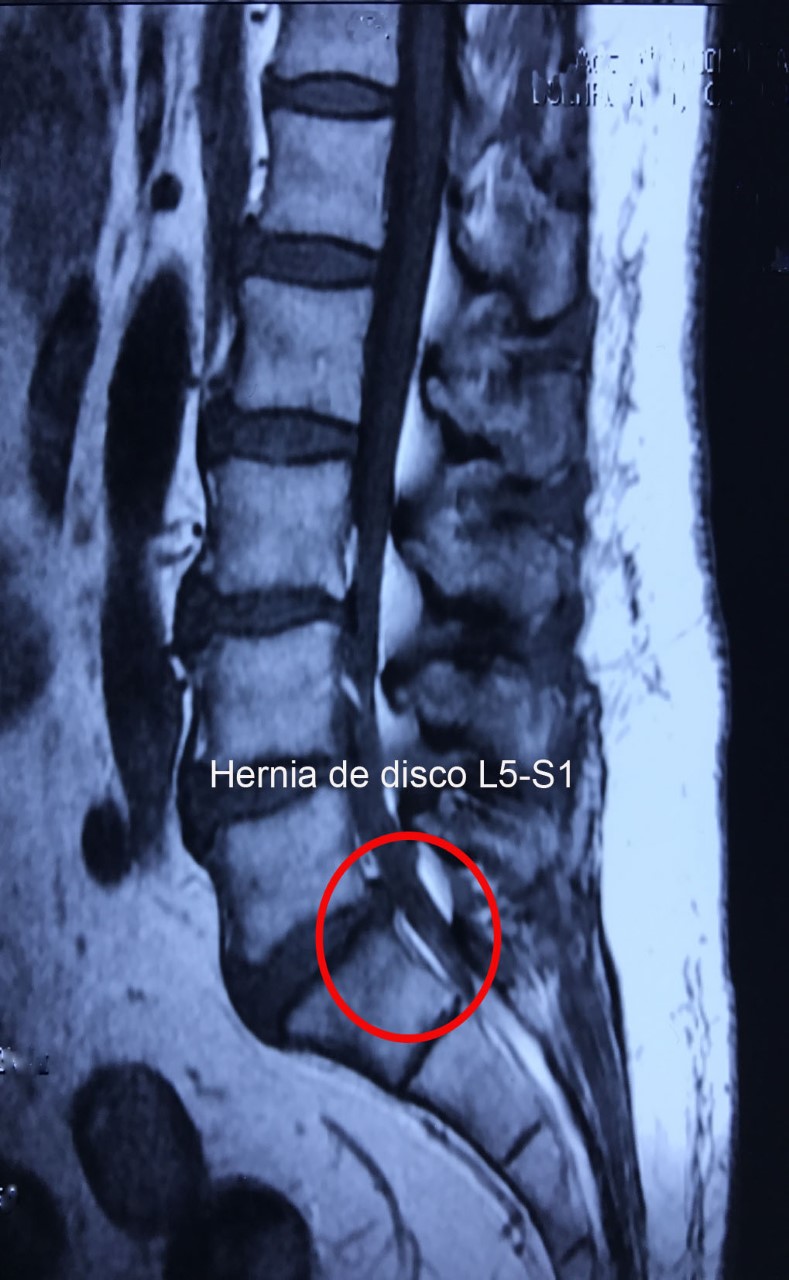

Es el dolor localizado en la parte baja de la espalda, cuyo origen puede ser uní o multifactorial, como por ejemplo una hernia de disco o un canal lumbar estrecho. La lumbalgia puede acompañarse con dolor en trayecto del nervió ciático.

Lo más importante del tratamiento es identificar la causa, por lo que un protocolo diagnóstico completo, el cual consta de la exploración física, radiografías y en algunos casos resonancia magnética y electromiografía, nos permitirá dar un tratamiento específico para mejorar el dolor.